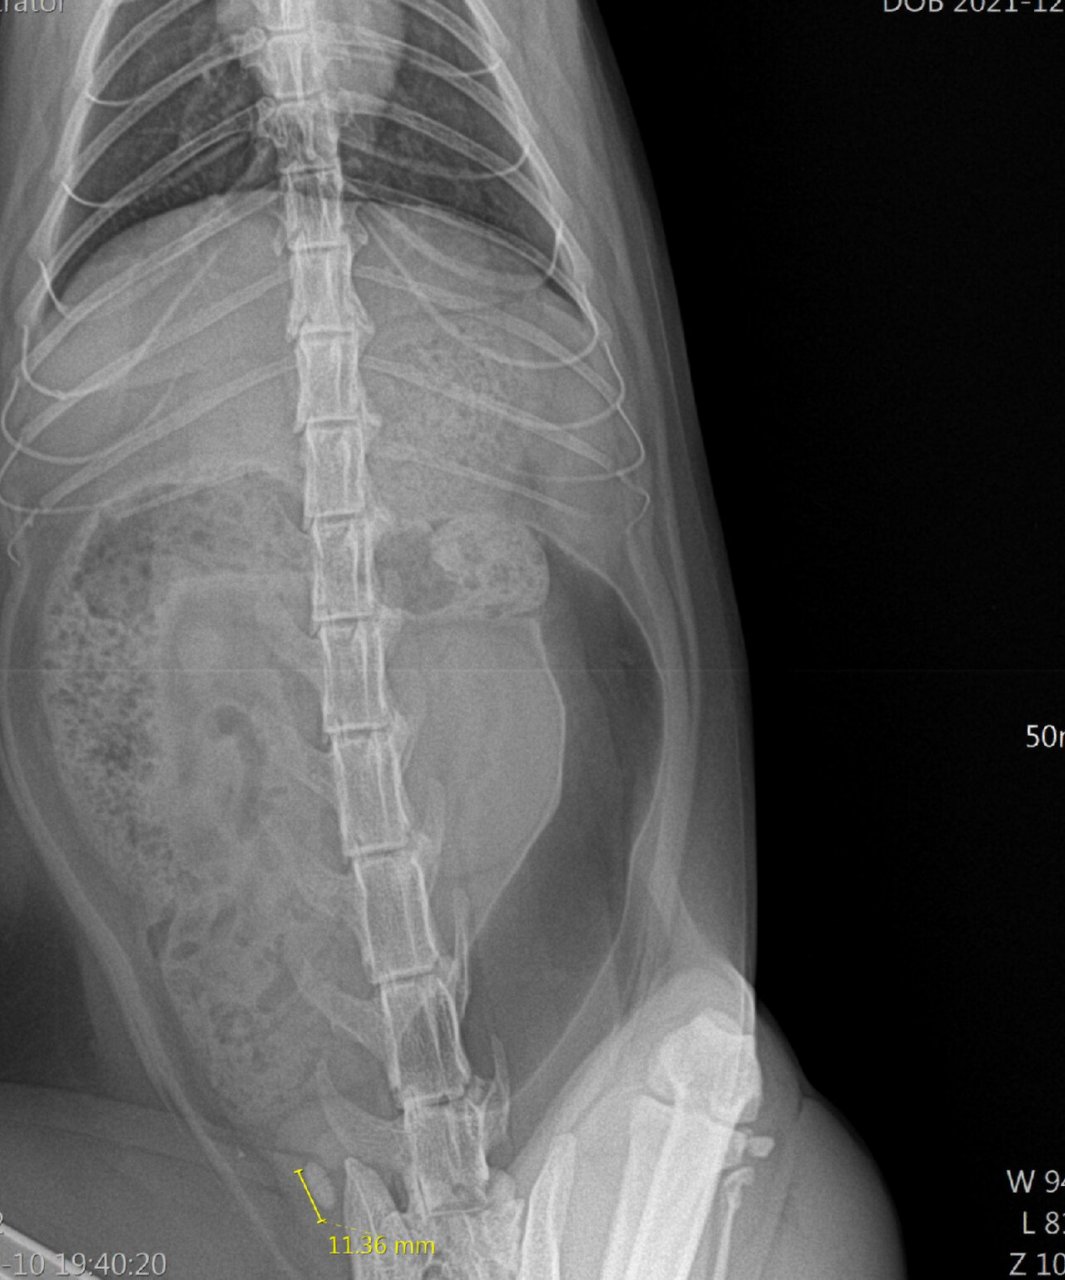

两个月前尿闭刚做完膀胱结石手术(图一二),现在又复发了(图三),医生说

图片尺寸1080x1439